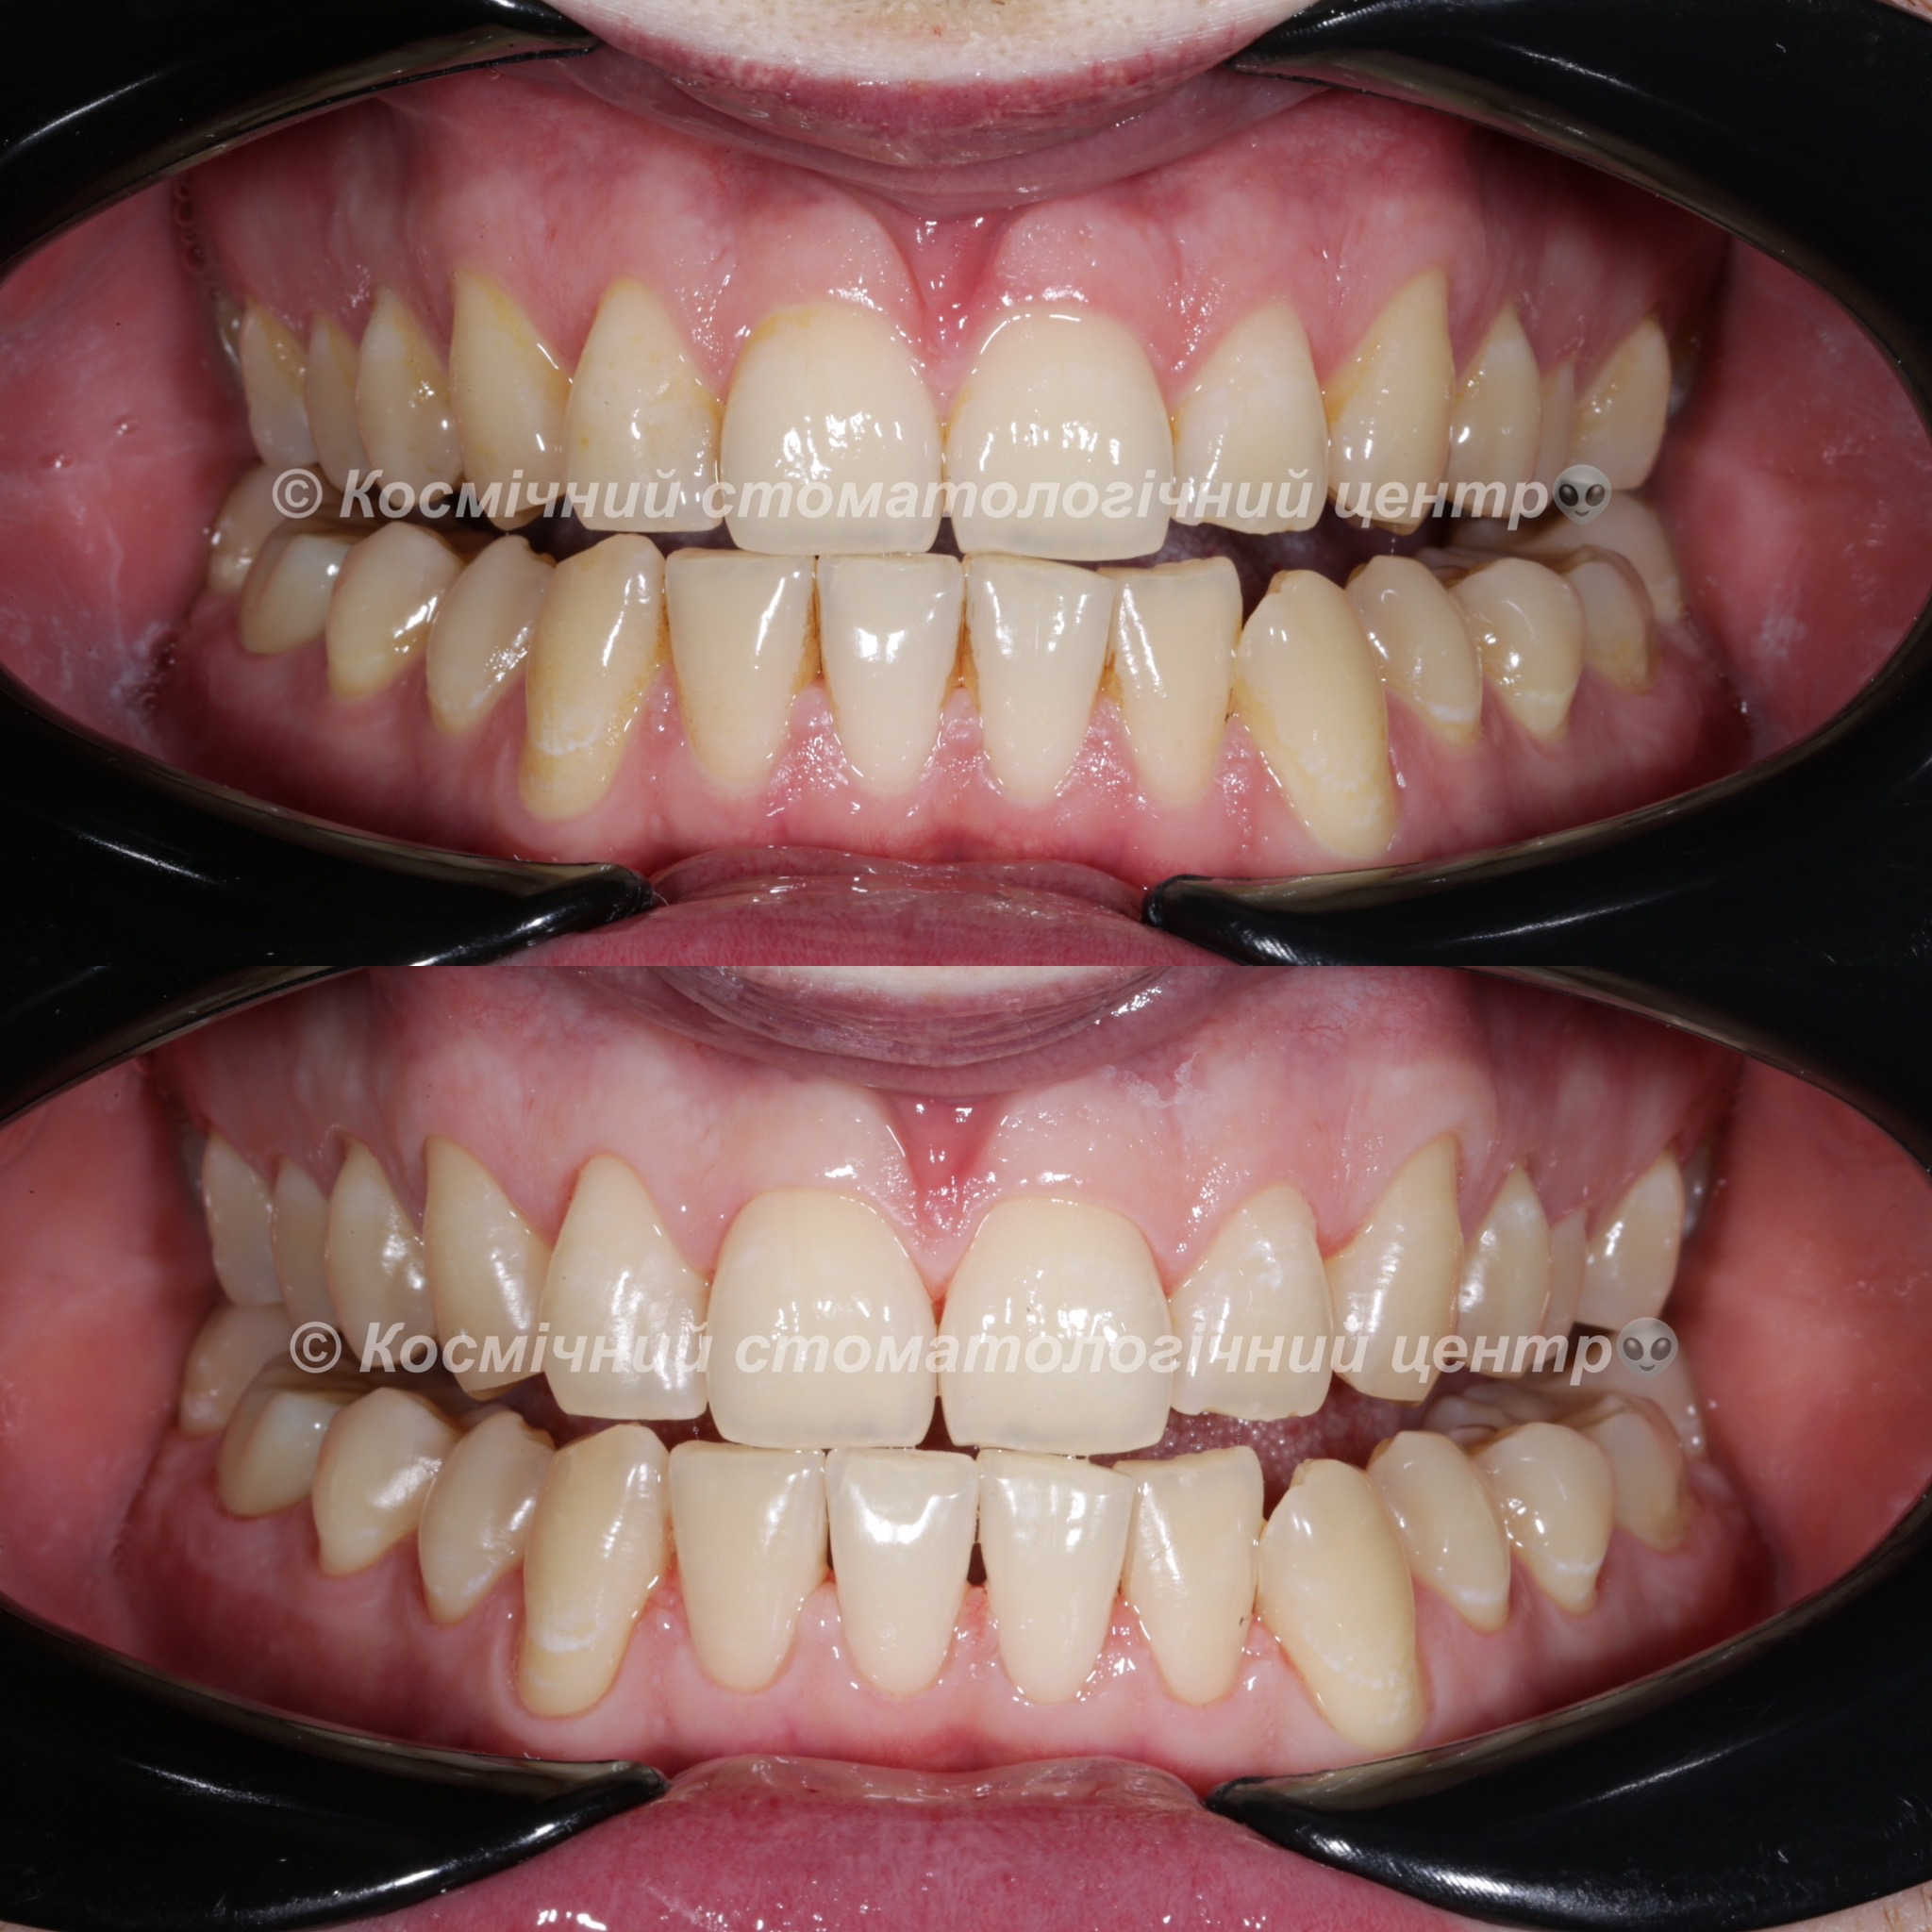

Галерея

Професійна гігієна (чистка) зубів складається з кількох етапів

• Комп'ютерна анестезія у разі підвищеної чутливості зубів.

• Зняття каменю ультразвуковим девайсом SIRONA (Німеччина) та звуковим наконечником KAVO (Німеччина) з електронним регулюванням потужності.

• Зняття каменю у важкодоступних місцях пародонтальними кюретами HU-Friedy.

• Зняття нальоту гігієнічними перлинами KaVo PROPHY pearls SUPRAGINGIVAL CALCIUM CARBONATE в індивідуальних пакуваннях із ароматом на вибір: персик, апельсин, м'ята, чорна смородина та нейтральний смак.

• Полірування швейцарською пастою Proxyt Ivoclar Vivadent для блиску та природної білизни.

• Діагностика прихованих захворювань ясен (скрінінг-тест).

• Покриття зубів фтористим лаком у місцях підвищеної чутливості;

• Ремінералізуюча терапія;

Повітряно-абразивна чистка зубів (Air Flow)

Завдяки піскоструменевому апарату з технологією Air Flow, який використовуючи тиск повітря та води, подає на зубну емаль спеціальний абразивний склад, зуби можна очистити не лише від м’якого нальоту, а й від пігменту. Для видалення нальоту, в Космічній стоматології Драганчука ми використовуємо KaVo prophy pearls supragingival calcium carbonateneutral.

Чистка зубів щіточками та пастами

Фінальний етап професійної гігієни - полірування спеціальними щіточками та пастою, щоб усунути мікротріщини та шорохуватості, що виникли після чистки та видалити залишки нальоту, що могли в них залишитись. Це дозволяє суттєво уповільнити формування нових відкладень.

Полірування зубної емалі гумками

Кінцеве полірування поверхні зубів проводиться із застосуванням різних насадок, зокрема спеціальних гумок, що надає зубам ідеальної гладкості та блиску. Спеціальні гумові насадки відмінно справляться з наданням естетичної довершеності твоїй посмішці.